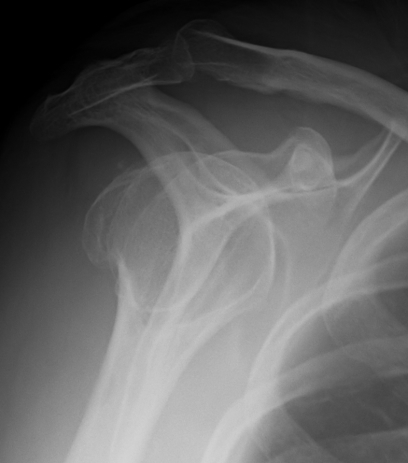

proximal humerus fracture Background ORIF with locking plate Arthroplasty Greater tuberosity fractures Lesser tuberosity fractures / avulsions Book traversal links for Proximal humerus fractures ‹ Pectoralis Major Tears Up Background ›